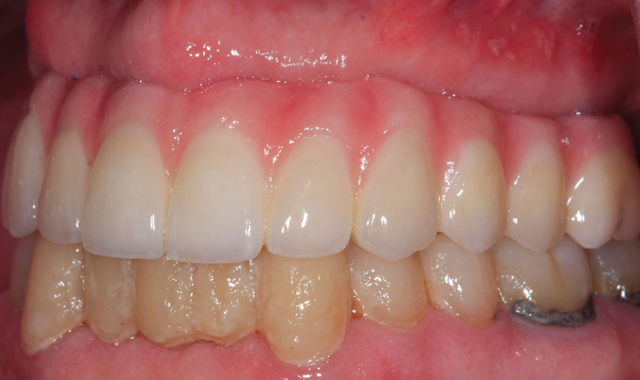

Fig. 14 Side view in the mouth

The finished restoration was photographed in the mouth after immediate try-in (Fig. 14).